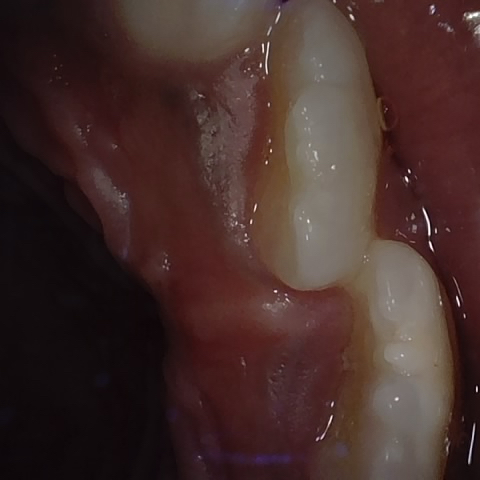

Annotated as "Good"